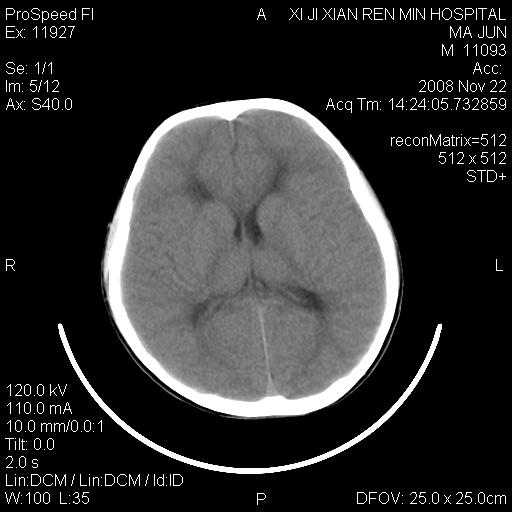

双侧侧脑室前角,三角区旁及半卵圆中心区白质呈低密度改变,半卵圆中心区病灶呈片状融合趋势,无软化征像,脑室无扩张,各神经核团无异常改变,脑皮质无萎缩等征像,结合病史考虑髓鞘发育不良性脑白质病,异染性脑白质营养不良可能性大.不除外多发性硬化等其他改变,建议磁共振检查

脑白质减少,双侧侧脑室额角旁及半卵圆中心可见对称性略低密度影,边缘尚清,考虑脑白质发育不良